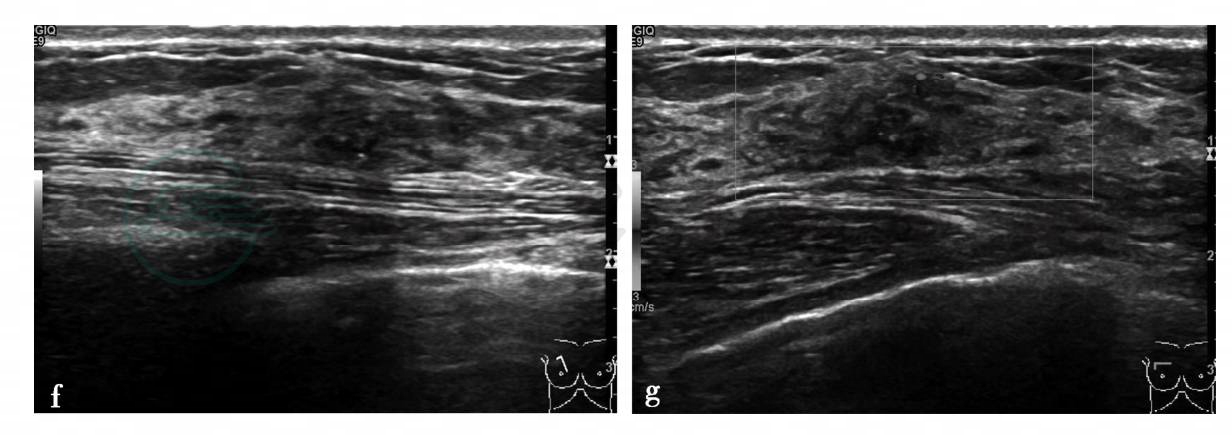

图2 图2f,右乳病变二维超声图。图2g,右乳病变彩色多普勒血流图。超声显示右乳稍内上方局限低回声区,范围约0.9cm×0.6cm,边界不清,内部回声不均匀,其内可见点状强回声。图2g,CDFI示可见较粗大血流信号